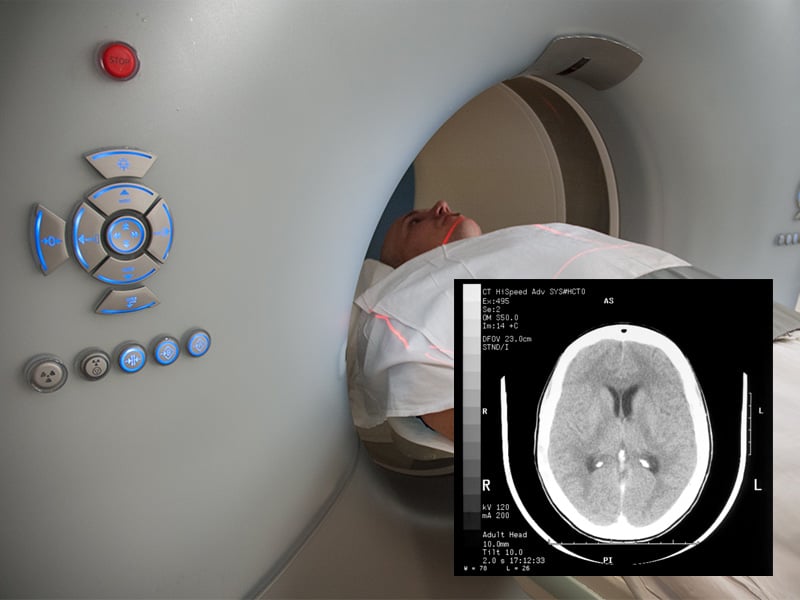

Computed tomography procedures use a rotating x-ray unit that takes hundreds of images of a body part in just a few minutes. The CT scanner obtains images of thin slices of anatomy at different levels throughout the body. A computer then stacks the slices and assembles them into one image.

CT head scan / Image © ASRT

CT head scan